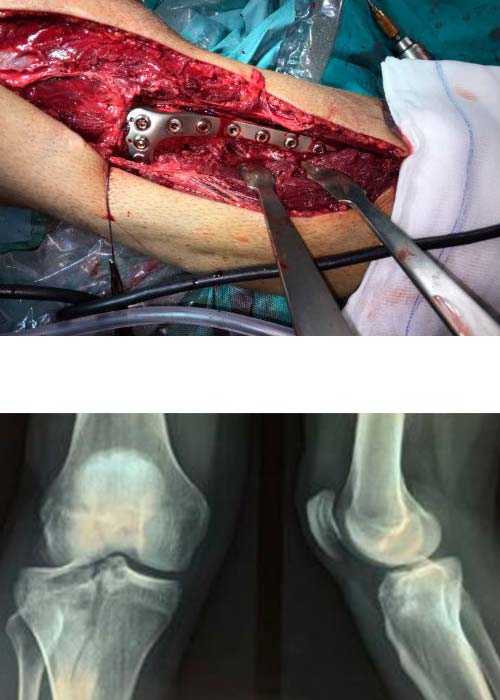

fractura-meseta-tibial-operatorio

Operación

Es intervenido quirúrgicamente a las 48 horas realizándose abordaje anterolateral de tibia proximal, reducción y fijación interna con placa lateral de tornillos bloqueados y no bloqueados de 4,5 mm.